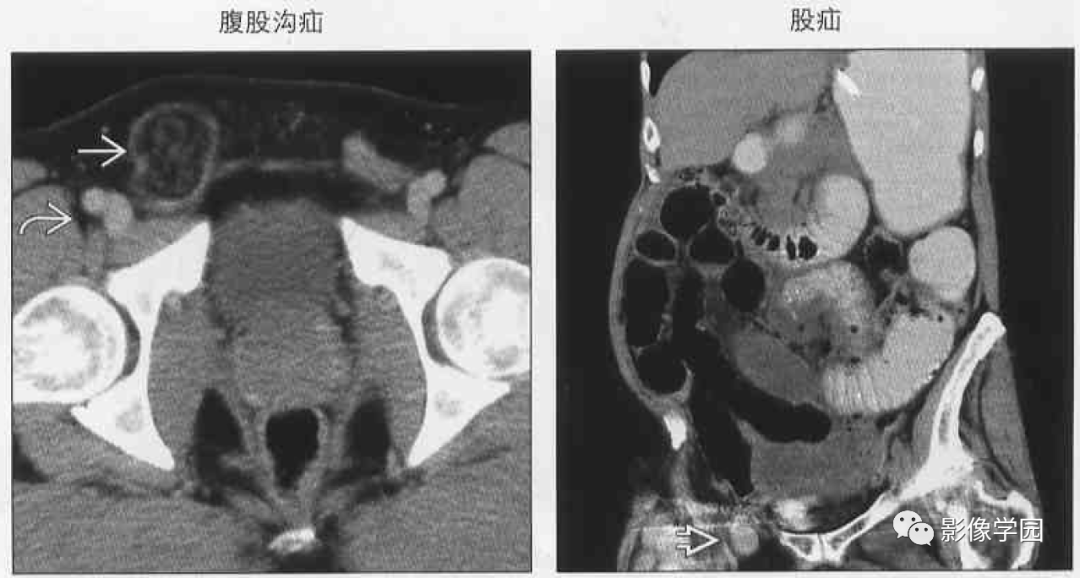

(左图)轴位cect显示腹 股沟疝疝囊内仅包含脂 肪组织,疝囊位于耻骨

图24 腹股沟疝